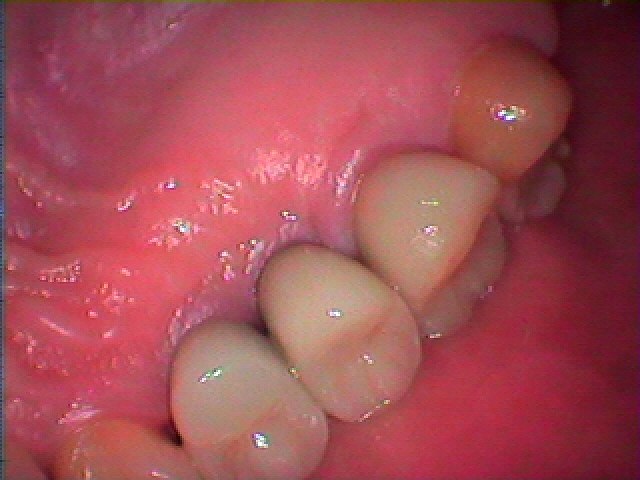

インプラントの最終補綴へ 埋入より3か月後になります|お知らせ |広島市安佐南区の歯科医院 インプラントの最終補綴へ 埋入より3か月後になります トップ お知らせ・ブログ お知らせ インプラントの最終補綴へ 埋入より3か月後になります インプラントの最終補綴へ 埋入より3か月後になります このように傷が治ります きれいに治っています カスタムアバットメントにて作成しています このように立ち上げています レントゲンにてもソーサライゼーションの起こりにくい埋入深さになります オールセラミックにて作成しています 抜歯窩にもドリリング時には足を取られ、上顎洞も持ち上げながら、 スペースが狭くなっていることもあり、5番は少し傾斜埋入となりました Web診療予約 初めての方へ 選ばれ続ける理由 院内設備について 歯が痛いしみる一般歯科 歯がぐらぐらする歯周病 健康な歯を保ちたい予防歯科 子供の虫歯予防をしたい小児歯科 銀歯をセラミックに審美歯科 白い歯を目指しませんか?ホワイトニング 矯正専門医がいるので安心矯正歯科 抜けた歯を補いたいインプラント・入れ歯 医院案内 スタッフ紹介 メリィハウス歯科クリニックオフィシャルホームページ ラベンダー歯科クリニックオフィシャルホームページ お知らせ・ブログ ホーム 診療科目 一般歯科 歯周病治療 予防治療 小児歯科 審美治療 ホワイトニング 矯正歯科 入れ歯・インプラント マウスピース矯正 初めての方へ 院長・スタッフ 設備紹介 医院案内・アクセス メニューを閉じる